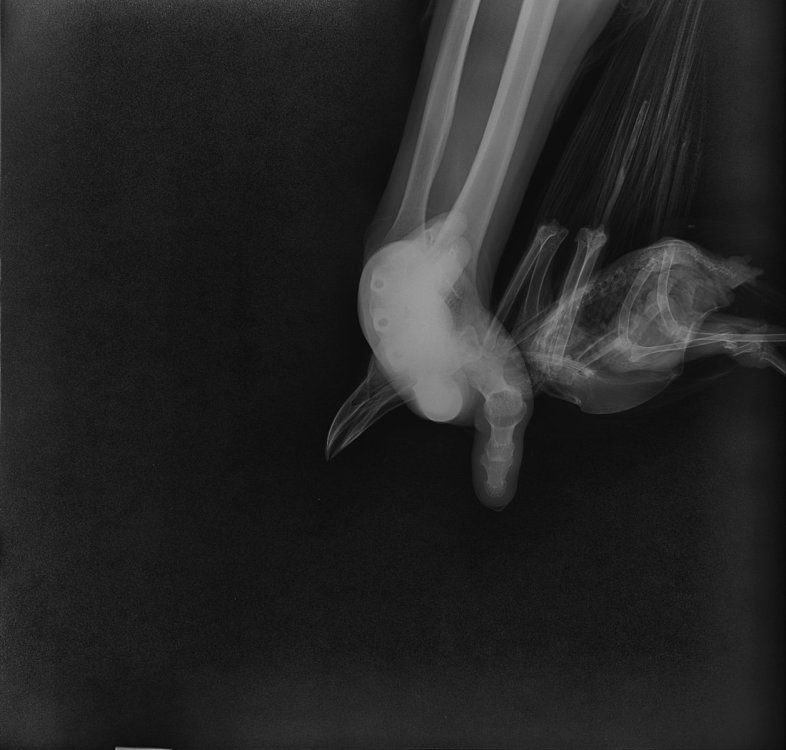

2. Перелом открытый, как выглядит (фото)?

20240905005_Дегтянникова_Ворона_20240905162112.jpeg

20240905005_Дегтянникова_Ворона_20240905162124.jpeg

20240905005_Дегтянникова_Ворона_20240905162136.jpeg

У меня остаются подозрения, что где-то есть открытая рана, личинки не могут быть просто так. По рентгену не вижу, где могла бы быть. Лучше обратиться к Zosia, чтобы посмотрела рентген, быстрее будет по Вацапу в ее профиле.